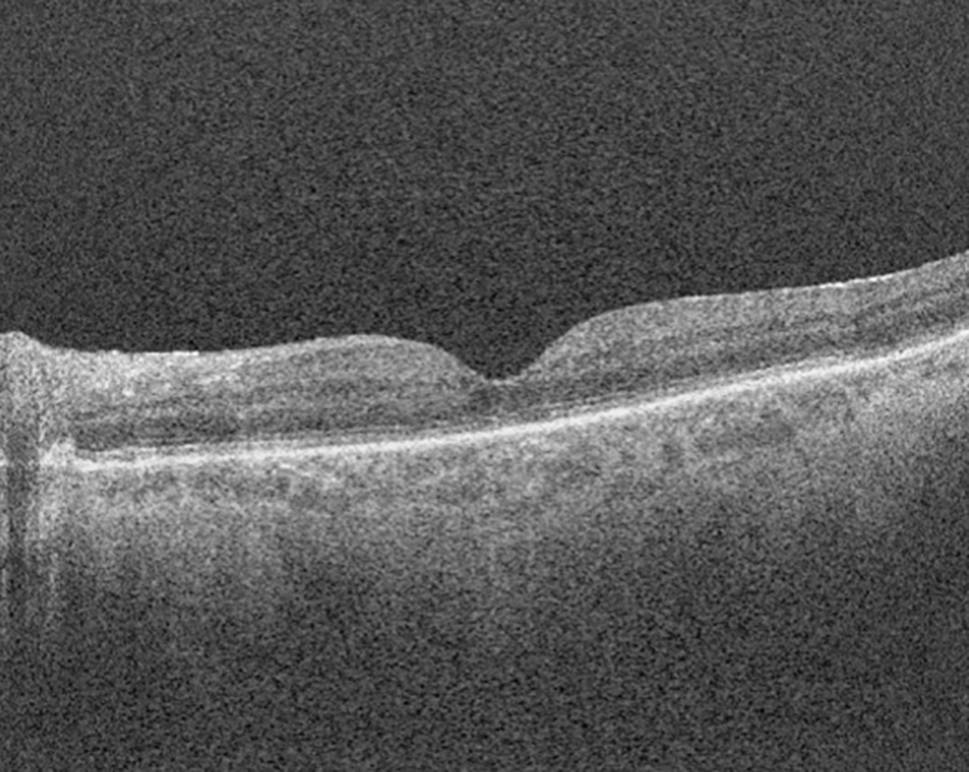

Fig. 10

Optical coherence tomography image demonstrating macula involvement in the retinal detachment in Fig. 9

Optical coherence tomography (OCT) is a noninvasive test that utilises light reflected to provide a cross-sectional image of the retinal layers [71]. It can assist in the detection of microstructural changes that are not always clinically evident, such as the presence of subretinal fluid at the macula in an RRD (“macula-on” or “macula-off”). These classifications have important implications for surgical timing and the visual prognosis. Macula-on RRDs typically have better VA on presentation and yield better visual prognoses. Surgery is typically performed within 24 h. Macula-off RRDs present with worse visual acuities and tend to have worse visual prognoses despite successful retinal reattachment [6].

Postoperatively, OCTs can also indicate important anatomic abnormalities after retinal reattachments, such as cystoid macula oedema, disruption of the ellipsoid zone/external limiting membrane, epiretinal membrane, disruption of retinal layers, retinal folds, outer retinal corrugations and residual subfoveal fluid [72]. These are important in explaining and predicting visual prognoses and metamorphopsia despite successful reattachment [71]. More recently, OCT angiography (OCT-A) has helped to predict visual prognosis after macula-off retinal detachment repairs, particularly due to the detection of an enlarged foveal avascular zone (FAZ) and reduced vessel density in the choriocapillaris [73].